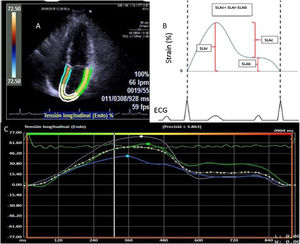

Deformation of the left atrium was determined (Fig. 1) using the syngo® Velocity Vector Imaging technology software. The echocardiographic view for the study was the apical 4-chamber. The endocardium of the left atrium was manually traced at the end-systole, and the edges of the endocardium were traced by the software through the cardiac cycle. The software took the R-R interval of the electrocardiogram pattern for deformation calculation. The deformation was evaluated as the global longitudinal strain and 3 values were calculated in the atrial deformation called: atrial longitudinal strain reservoir (ALSr),duct (ALSc) and booster pump (ALSb). The ALSr corresponded to the value from the highest peak of the reservoir phase, the ALSb to the highest peak of the booster pump phase and the ALSc to the difference between the ALSr and the ALSb. Furthermore, the value of the rate of deformation was reported, defined as the strain rate. The LAGLS under 35% was used to define a deformation of the depressed atrium reflecting a change in the atrial contraction and stiffness.20

A) Four-chamber apical view image where the edges of the left atrium are determined for strain calculation. B) Graphical representation of the left atrium strain in the whole atrium cycle. The ALSr corresponded to the value from the highest peak of the reservoir phase, the ALSb to the highest peak of the booster pump phase and the ALSc to the difference between ALSr and ALSb. C) Representation of the strain report of the left atrium of the VVI software.